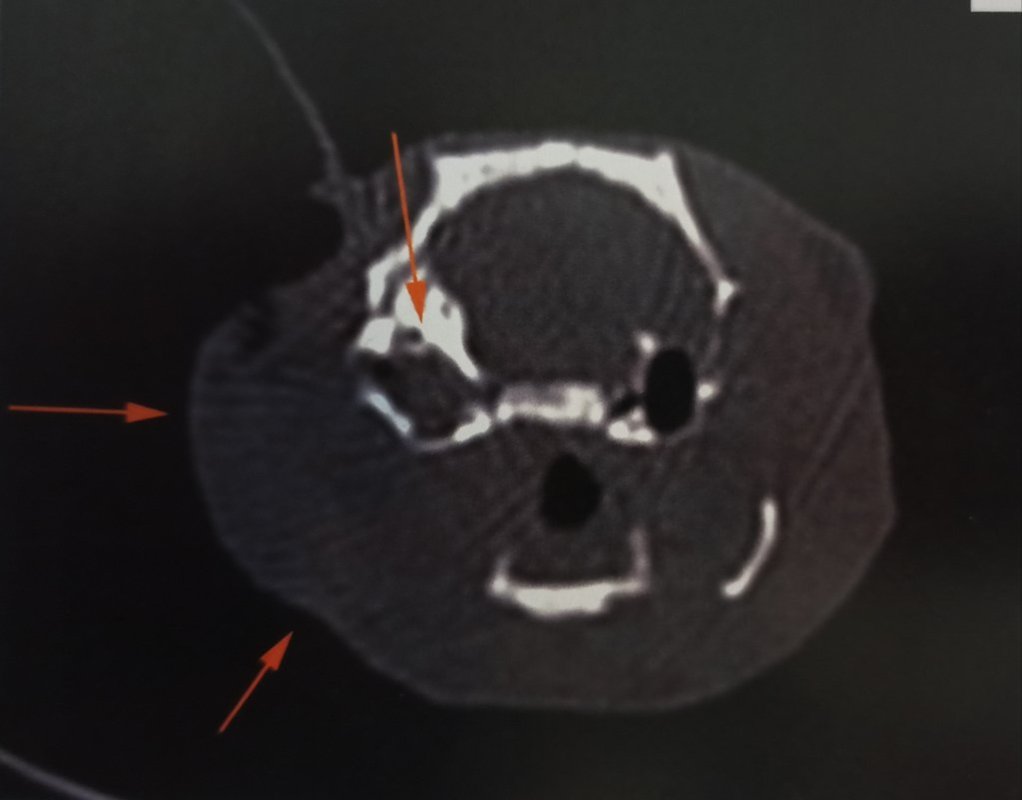

Alors figurez-vous que... C'est une otite ! Mais ce n'est pas réjouissant pour autant :|

J'ai finalement accepté le scanner, ça a été fait aujourd'hui, ils l'ont gardé la nuit d'avant et en ont profité pour le requinquer en nourriture et le réhydrater pour qu'il soit autant en forme que possible pour l'anesthésie.

Quand je l'ai amené hier, la véto m'a dit que si le produit de contraste est correctement injecté, normalement on ne devrait pas rater une éventuelle TH (sauf si toute toute petite mais dans ce cas peu probable que ce soit ça le problème). J'y connais à peu près rien en imagerie médicale, mais peut être que la largeur de coupe dépend aussi de la machine de la clinique ? Dans ce papier, ils ont fait passer un scanner avec injection de produit de contraste à 25 rats présentant des symptômes de TH, et ils ont pu voir une tumeur chez 20 d'entre eux. Pour les 5 autres ils parlent d'otite mais j'ai pas vraiment compris si le diagnostic avait été confirmé.

D'après son expérience, en cas de troubles neurologiques chez le rat, lorsqu'ils font un scanner elle estime qu'ils trouvent environ 1/3 d'otites et 2/3 de TH. Elle a reconnu qu'il n'avait pas tous les symptômes habituels de l'otite, mais elle ne voulait pas l'exclure, car parfois ça peut être un peu atypique.

Et effectivement, pour le coup c'était ça. On ne le voit pas de l'extérieur mais il y a un gros gonflement autour de la bulle tympanique, c'est ça qui a décalé sa mâchoire en fait, et malheureusement cela a également atteint le cerveau...

Une chirurgie est possible pour la partie hors du cerveau, ce qui pourrait permettre de le rendre plus confortable pour manger, mais ce n'est pas sans risque d'empirer les choses, et quoi qu'on fasse on n'a pas d'espoir de guérison, seulement de lui faire gagner un peu de temps en gérant au mieux douleur et inconfort. Elle m'a fait une prescription de tramadol à ajouter au reste s'il semble avoir mal.

Je vous partage les images parce que vu le prix qu'elles m'ont coûtées autant que tout le monde en profite ><